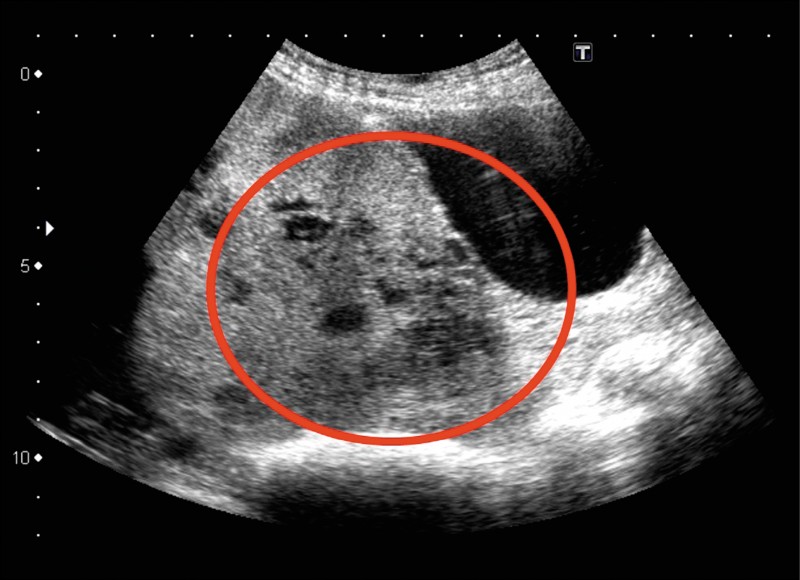

前置胎盤とは,内子宮口またはその付近を覆って胎盤が付着している状態である。. 典型的には妊娠20週以降に痛みを伴わない鮮紅色の性器出血が起こる。. 診断は経腟または腹部超音波検査によって行う。. 治療法は,妊娠36週前で少量の性器出血には安静.. 正常の位置に付着している胎盤が、赤ちゃんが生まれる前に子宮壁から部分的、あるいは完全に剥がれ落ちてしまう状態を常位胎盤早期剥離といいます。常位胎盤早期剥離の頻度は、全分娩中0.5~1.3%とされていますが、年々増加傾向にあるとの報告もある.